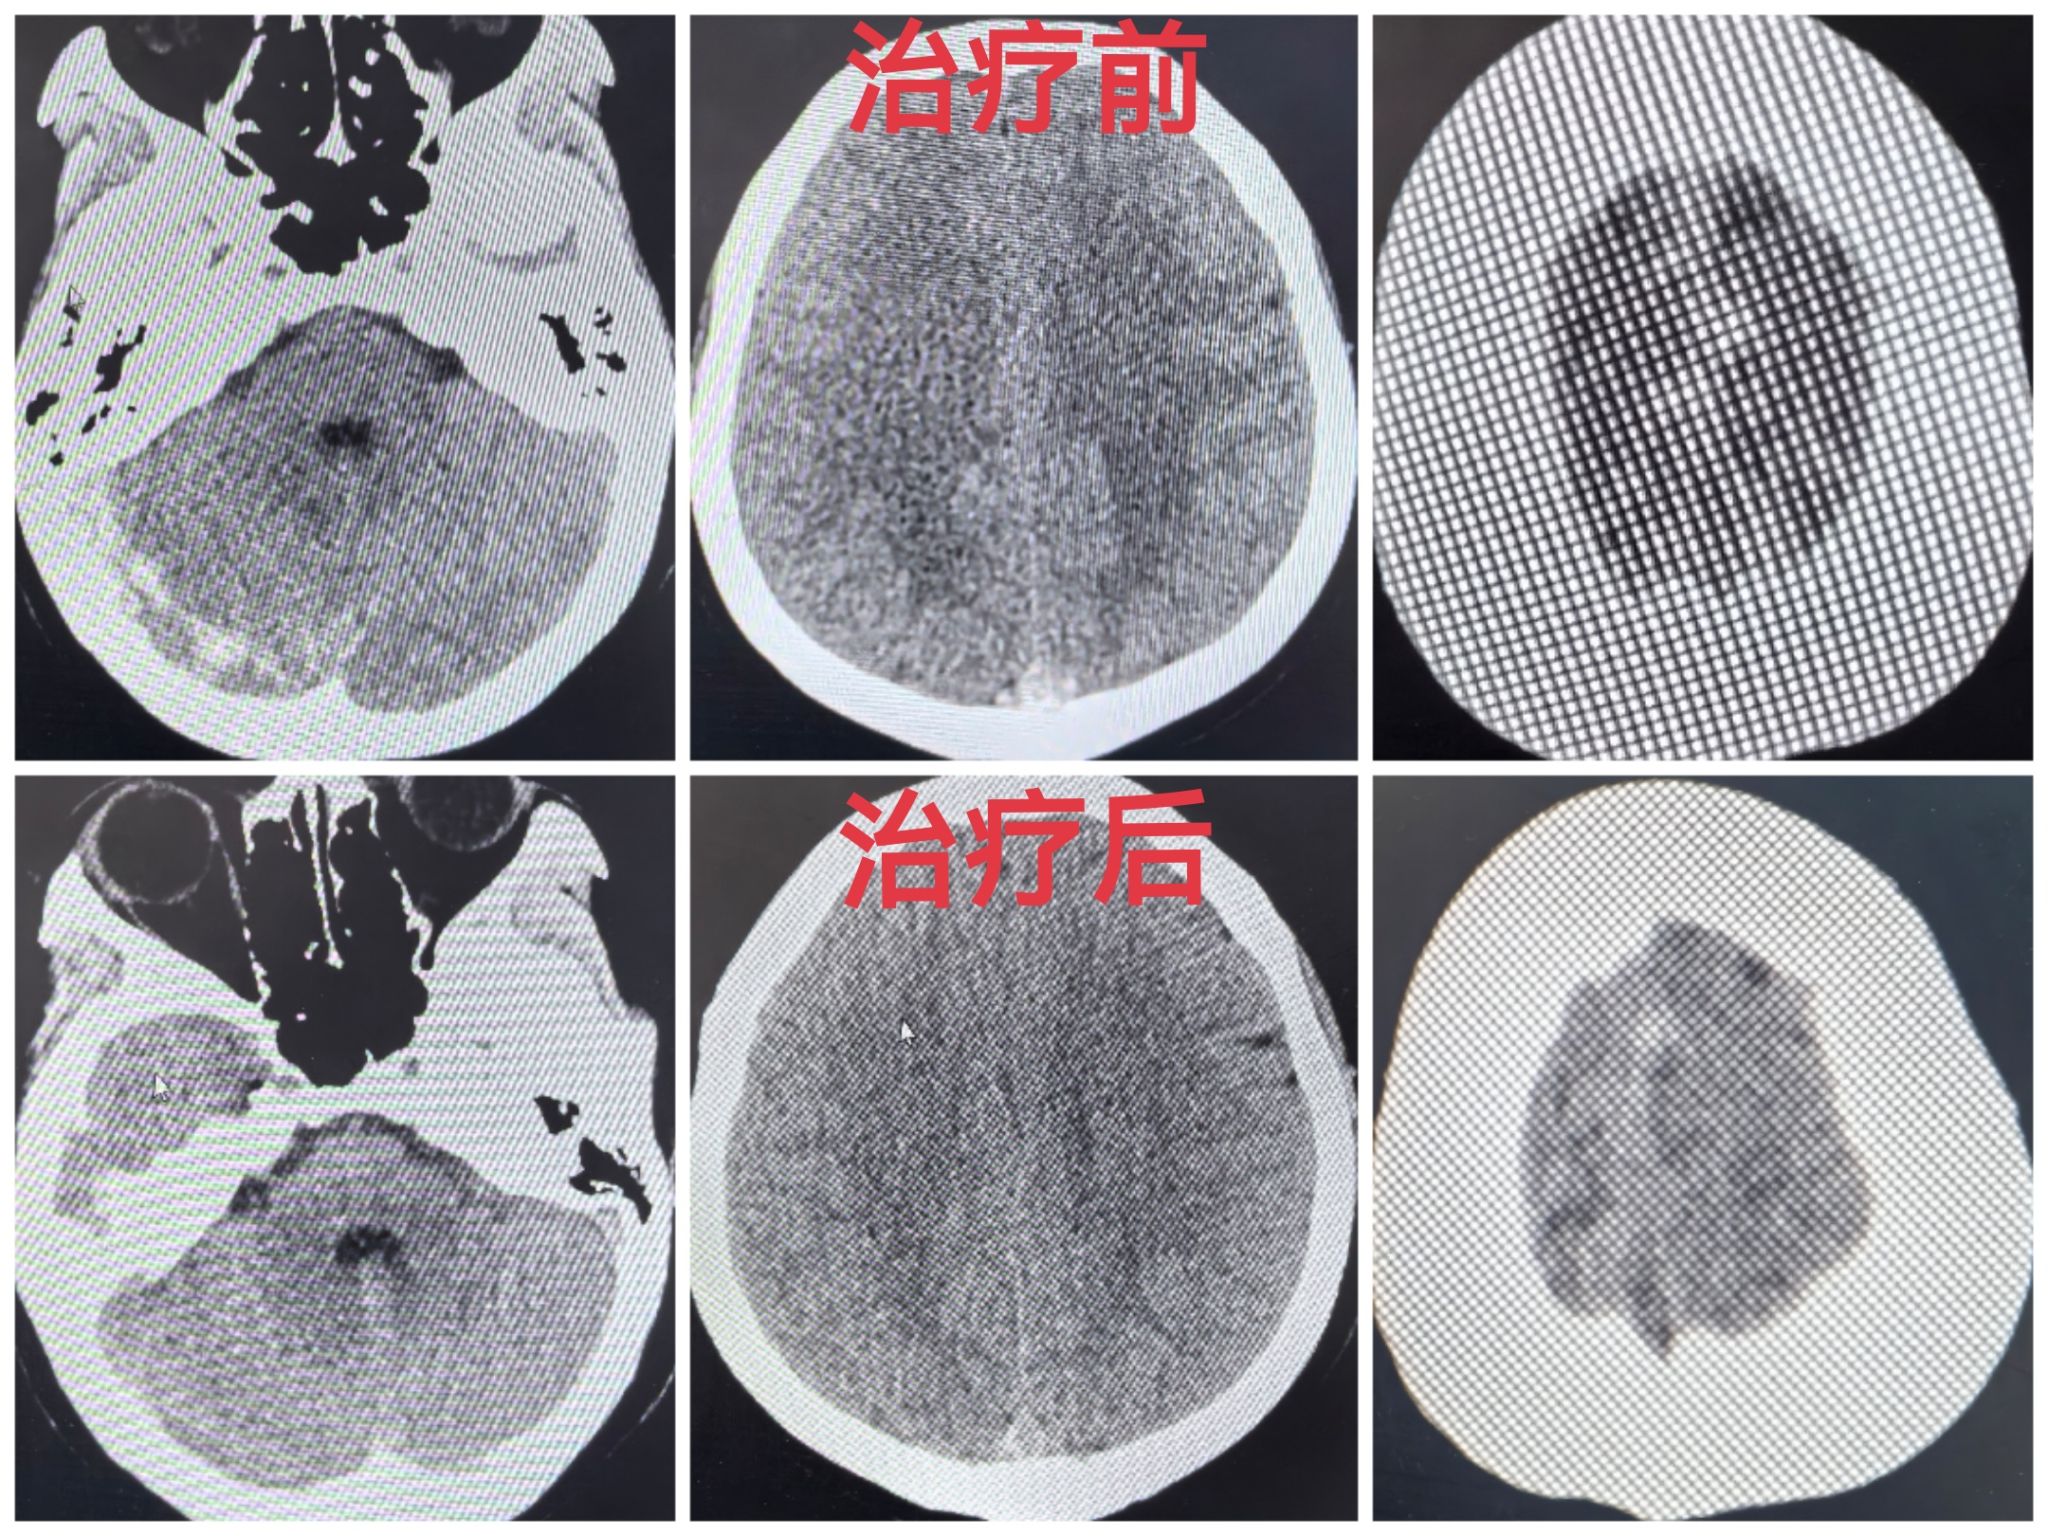

成功救治CVST患者

患者,女,28岁,进藏1周并伴发肺水肿,头部持续剧痛,全身无力,合并恶心呕吐等症状,在外院按高原反应治疗无效后急诊转至山南市人民医院,给予完善头颅CT检查。援藏医疗专家张子焕与科室史睿主任阅片后考虑CVST伴出血可能,需要急行全脑血管造影明确诊断。后立即启动脑卒中应急处置预案,联动介入中心、检验科及放射科等科室开放绿色通道。在多学科配合下,患者于1小时内完成院内急救及术前相关检查并安全送至介入手术室,全脑血管造影进一步证实该患者为CVST。随后结合血栓位置、范围,按照治疗指南,给予规范抗凝治疗,翌日患者症状即减轻,提示治疗有效,而后逐渐好转,直至完全缓解。后复查全脑造影术,提示颅内静脉窦再通、血栓消失,治疗效果良好。